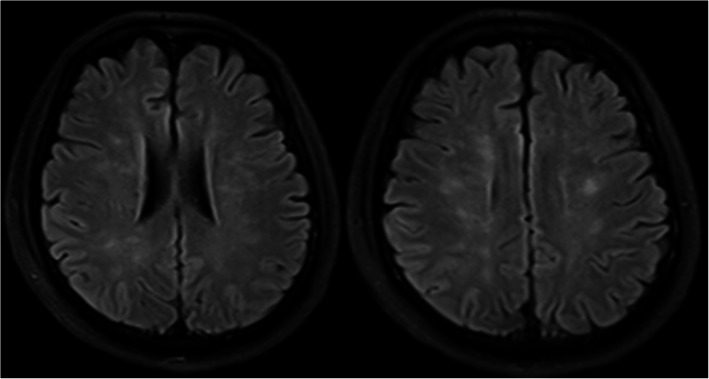

Bilateral lower extremity X-ray and pelvic CT in this patient showed multiple fractures of the bilateral lower extremities and pelvis. Head MRI showed multiple small lesions in the whole brain consistent with a “star field” pattern (Fig. 1), including high signals on T2-weighted (T2w) and fluid-attenuated inversion recovery (FLAIR) images in the bilateral centrum semiovale; both frontal, parietal and occipital lobes; and brainstem, cerebellar hemisphere, and deep and subcortical white matter. Head MRI was re-examined 15 days after admission to our hospital and revealed that the signals of these lesions on T2w and FLAIR images were slightly decreased (Fig. 2). Continuous electroencephalogram (EEG) monitoring showed generalized slow waves without epileptiform discharges. Bedside transthoracic echocardiography of this patient was highly suspicious of a patent foramen ovale. However, the transesophageal echocardiogram with bubble study failed to demonstrate an intracardiac defect or arteriovenous malformation (AVM) in the lung, further supporting a biochemical process.

Fig. 2.

Head MRI repeated 15 days after the previous head MRI showed the signals of the lesions on T2w and FLAIR images were slightly decreased